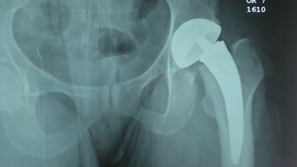

Good fit of final stem.

Stability was very impressive |

Trial neck off the final implant then 8 mm varus neck was chosen for final implantation.

Pt. doing well first day post-op. Saving all the lateral structures was very impressive.

Obvious as we new there would be outliers this first case confirms Australian experience that a smaller size may be needed and would more than likely be a monoblock neck design.

In both of these cases with tight fit cortical bone needs to be shaped to fit the medial curve and preparations for the differential size between the rasp and implant with the T-back. More experience is needed but possible additional preparation for the definitive stem in very tight situations may need to be addressed. Over all impression was good and basic instruments work well and the initial stability of the implant is impressive.

We did not have any problem with the angle of the neck cut as we paid special attention to that. You do need to be done to the bottom of zone A top of zone B (8 mm down from sub cap to ensure your neck length is not too high.